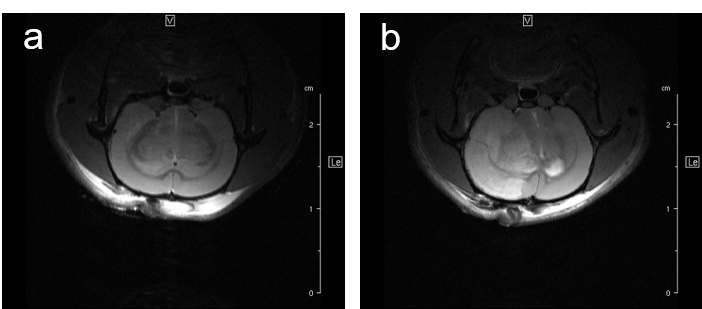

MRI may be used to quantitatively measure lung tumor burden and to follow up e.g. tumor growth. Images of a transgenic mouse model of hyperproliferation in the lung show clearly the replacement of the lung parenchyma Fig. 5.

Fig. 5: Mouse lung MRI. Exemplary axial MR-images of a mouse lung with hyperplasia: (a) respiratory-gated UTE-3D sequence with a repetition time of 8.0 ms, echo time of 20 µs, slice thickness/interslice distance: 0.39/0.39 mm, field of view 2.50x2.70x5.00 cm3 and a matrix of 128/128/128 and (b) respiratory-gated ZTE-3D sequence with a repetition time of 4.0 ms, echo time of 0 µs, slice thickness/interslice distance: 0.16/0.16 mm, field of view 3.00x3.00x4.00cm3 and a matrix of 256/256/256.